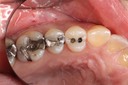

Frank Fukuda #30 finish

Frank Fukuda #30 buccal

Frank Fukuda #30 combined view